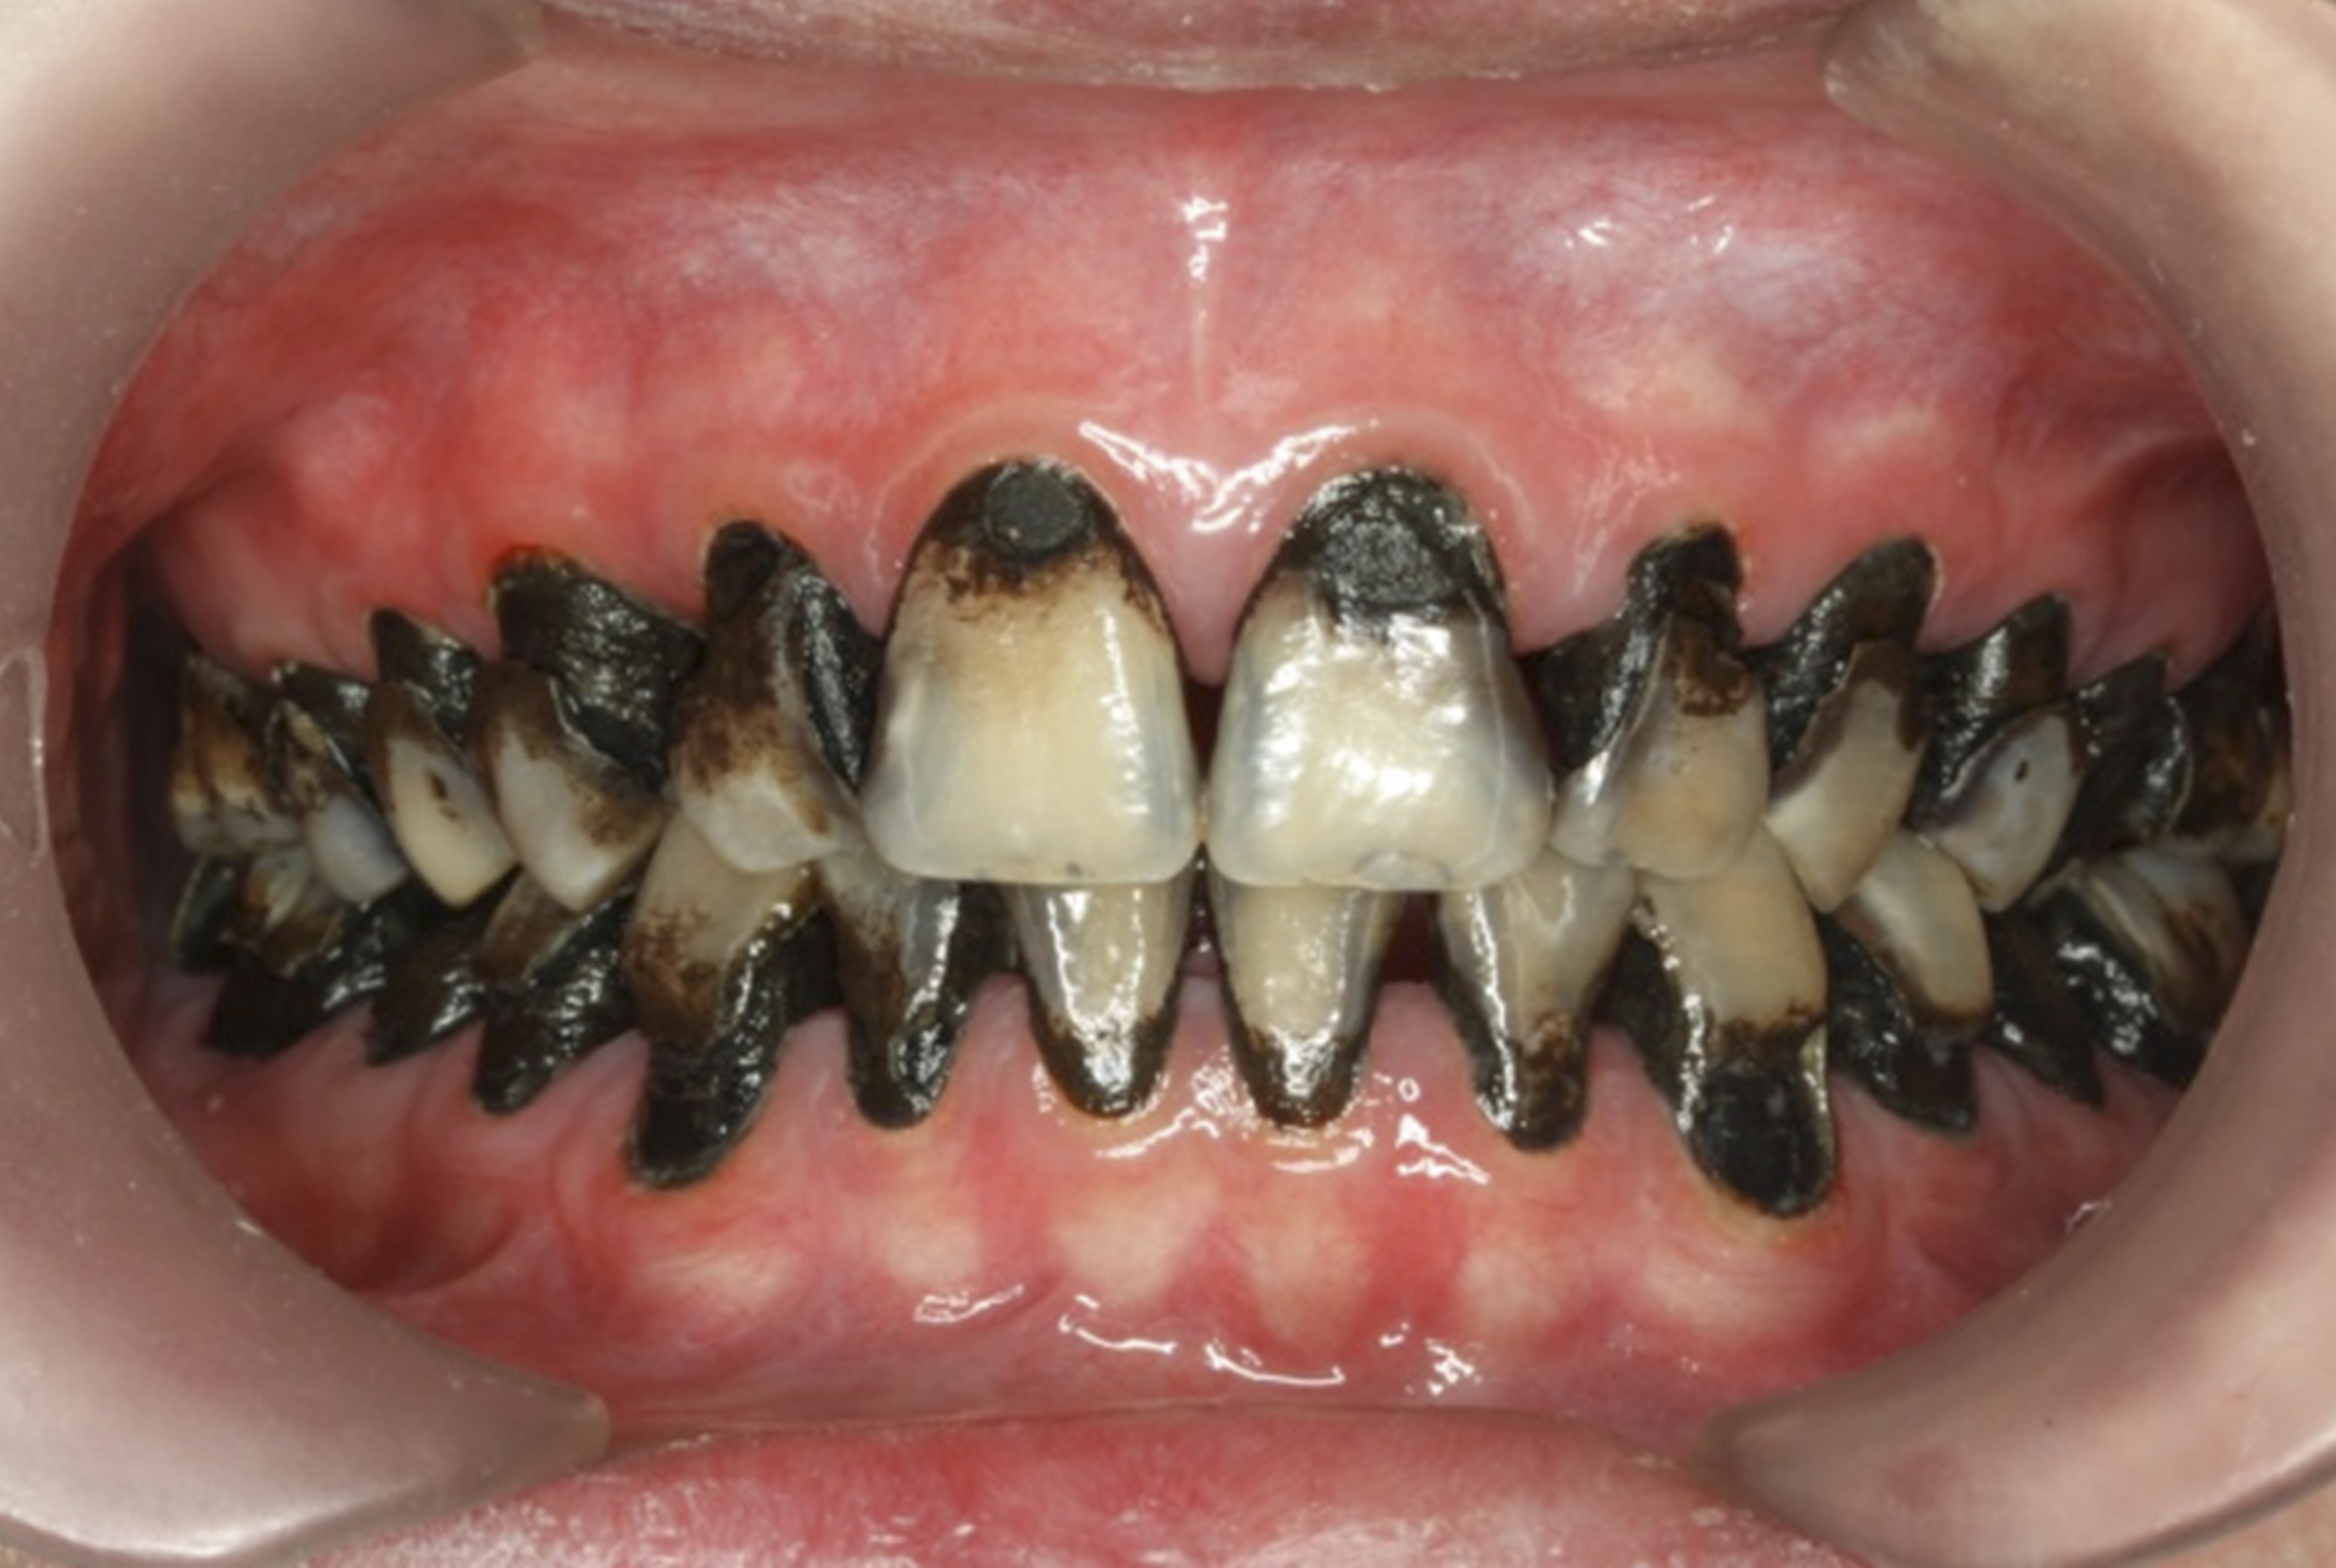

The inherent disadvantage of SDF is that the caries lesions will be stained black after SDF application. SDF stops caries progression by forming a hard, blackened, impermeable layer on the tooth surface that is resistant to caries (Figure 5 through Figure 9). The authors’ clinical observations are that the darker the color, the more likely the caries arrested. Some patients may not be pleased with the esthetics of this treatment outcome; therefore, it is important to inform the patients and parents (for child patients) about this treatment outcome. Moreover, SDF can stain clothes and the skin of the body. Though it does not cause any pain or damage, an SDF stain on skin cannot be easily washed away. It takes around 7 days for it to disappear, and the stain on clothes is permanent.22

There is no consensus on the frequency of application, and 38% SDF has been used annually or biannually on clinical trials in children23,31,33,34 and in elderly.30,35 Yee and his co-worker found one-off application of 12% SDF was ineffective in arresting caries in children.31 The present authors applied 38% SDF weekly for 3 weeks to speed up the process of caries arrest and for treatment of rampant caries.36 One of the present authors’ case reports demonstrated that three weekly applications of 38% SDF can arrest rampant caries and relieve pain from hypersensitivity on a teenager. The SDF-treated caries were found arrested, and they turned coal black in appearance (Figure 9).

Fig 8. Use of 38% SDF to arrest rampant caries in a young teenager. Fig 8: Pre-treatment intraoral frontal view of rampant caries. Fig 9: Frontal view of arrested caries after consecutive application of SDF for 3 weeks. (images from Chu, et al, 201436 [reprinted with approval])

Figure 8

Fig 9. Use of 38% SDF to arrest rampant caries in a young teenager. Fig 8: Pre-treatment intraoral frontal view of rampant caries. Fig 9: Frontal view of arrested caries after consecutive application of SDF for 3 weeks. (images from Chu, et al, 201436 [reprinted with approval])

Figure 9